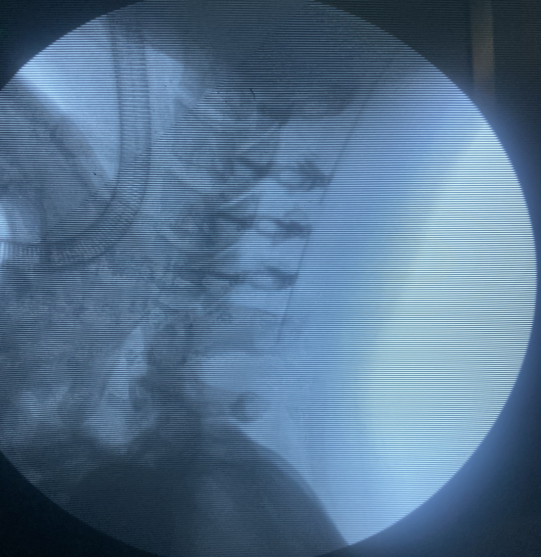

應(yīng)用效果展示